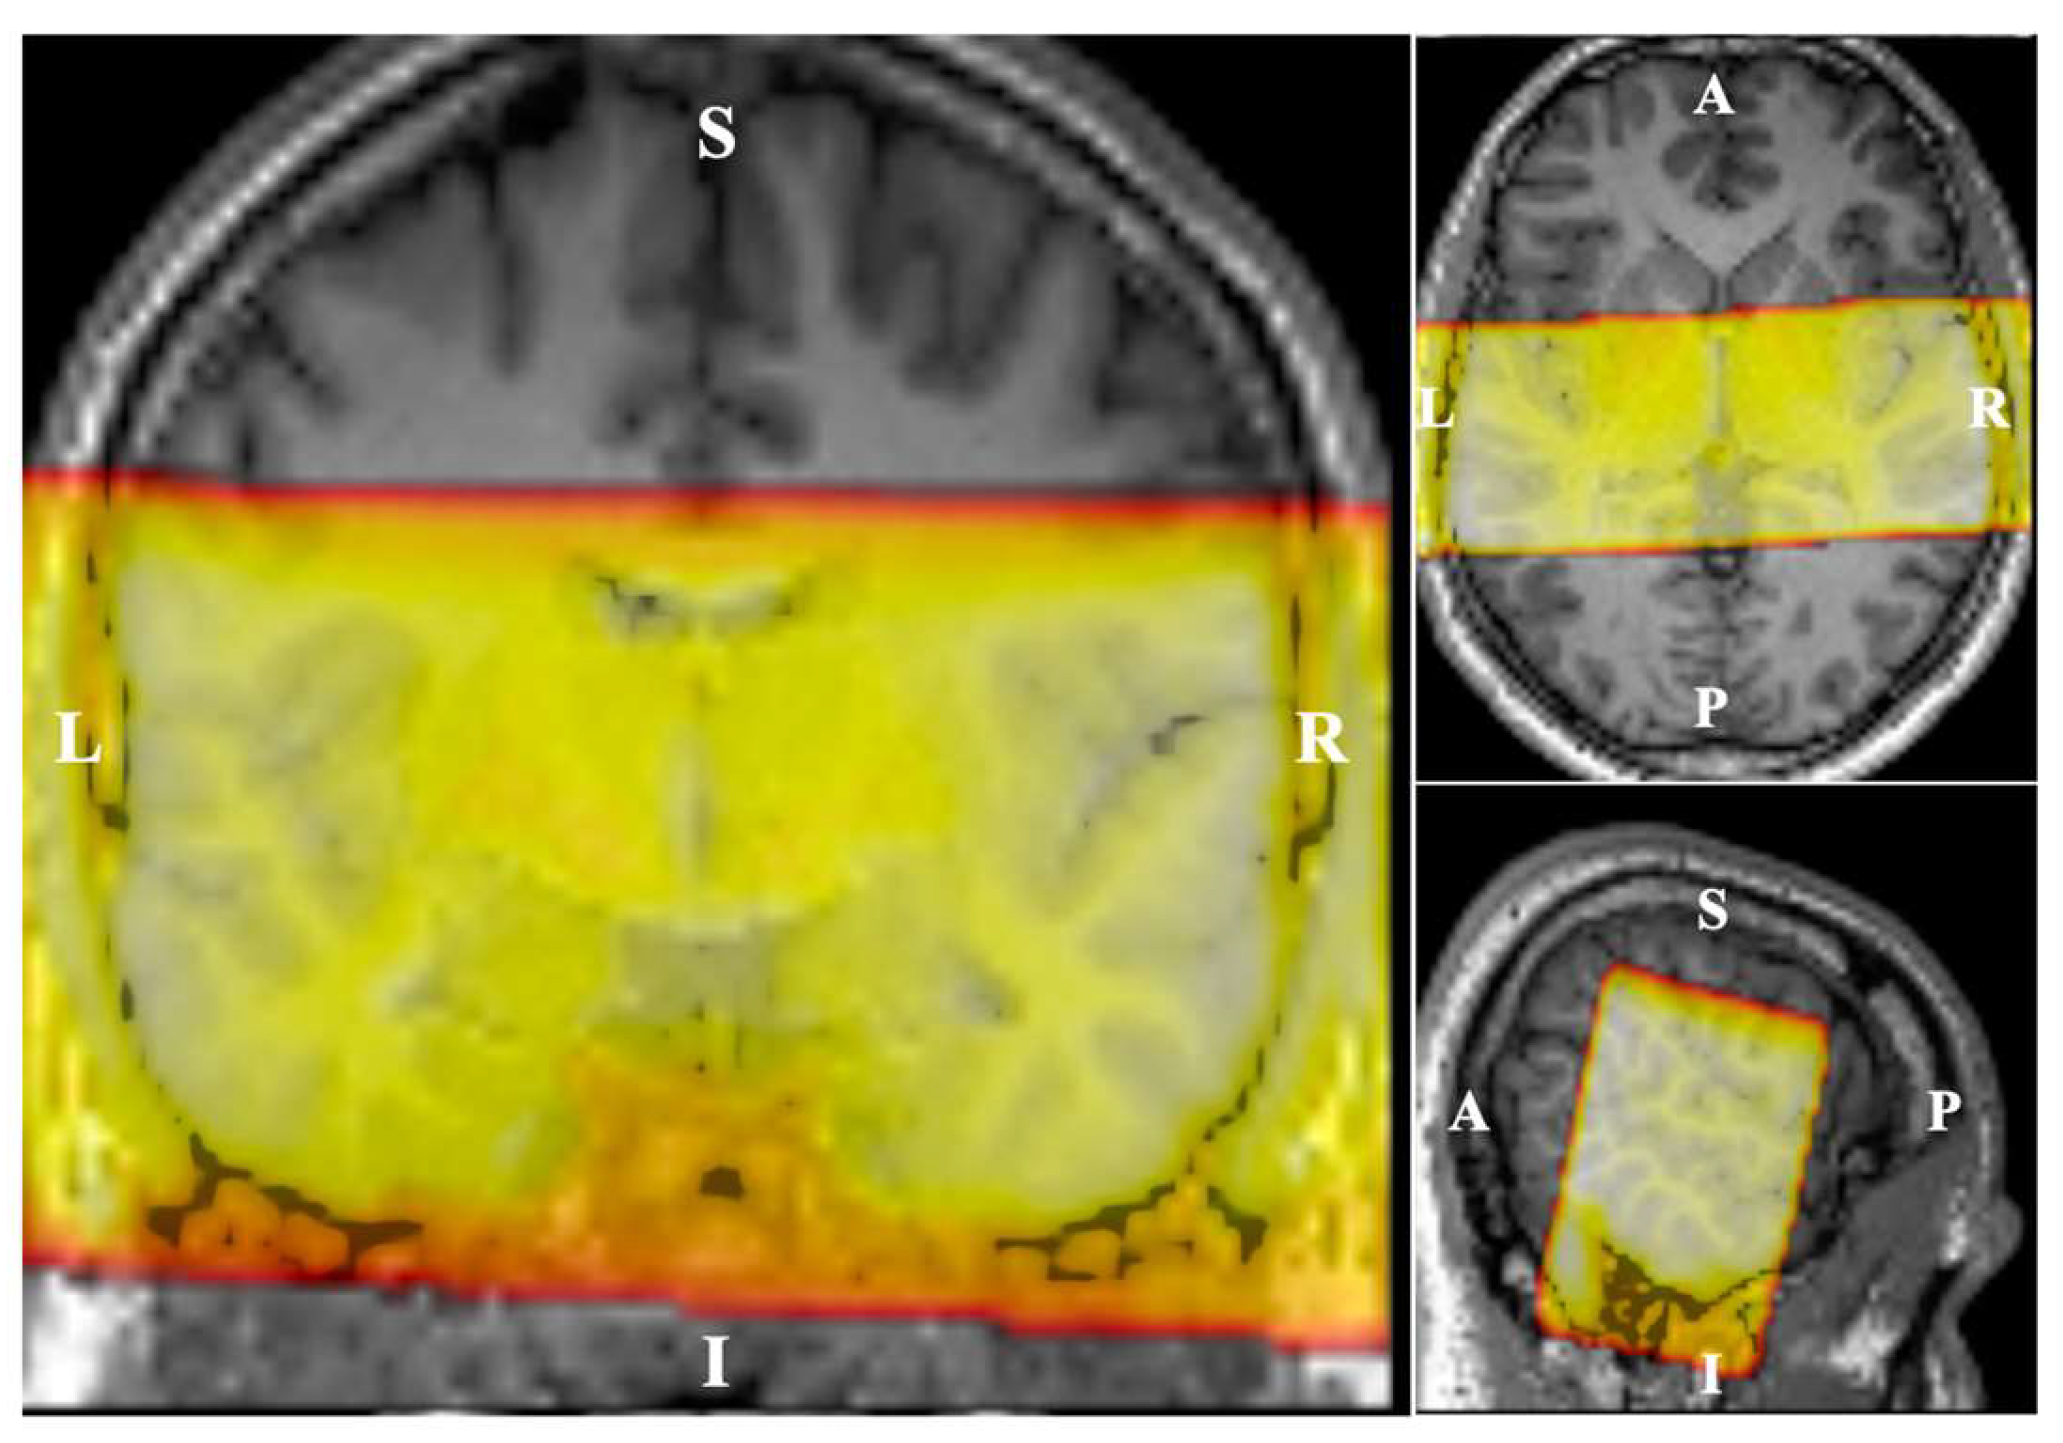

2.3. Imaging Paradigm

The MRI data were acquired using a 3-Tesla scanner (MAGNETOM Prisma, Siemens Healthineers, Erlangen, Germany) equipped with a 64-channel phased array head coil. A T1-weighted image (MPRAGE) was acquired for each subject (TR = 2300 ms, TE = 2.98 ms, FoV = 256 mm × 240 mm × 176 mm, 176 slices, 1 mm3 isotropic voxel) for anatomical reference. Echo-Planar-Imaging with reduced field of view in two dimensions (Siemens ZOOMit technique, Figure 1) was used to acquire the functional images (TR = 10s, TA = 2.97s, TE = 30ms, FoV = 192 mm × 84 mm × 176 mm, 29 coronal slices, 2 mm3 isotropic voxel). A sparse sampling method (6s sound stimulation scanner down) was used to prevent interference of scanner noise on the auditory cortex response [18]. For each subject, two runs of functional MRI were performed, 127 brain volumes each. Within one run, each frequency was monaurally presented 14 times to each ear. Additionally, a “silence condition” (no sound played) was presented 15 times, randomly distributed across the full run. A single EPI volume with the opposite phase-encoding direction was acquired after each functional run to allow geometric distortion correction. A T2-weighted image (TR = 1000 ms, TE = 127ms, FoV = 192mm × 84mm × 96mm, 96 slices, 1 mm3 isotropic voxel) with the same FoV as the functional scans was acquired to aid the registration of the functional images to the structural image.

Figure 1. Field-of-view (FoV) in functional MRI. The fMRI scans were performed coronally with FoV cropped in the superior-inferior direction.

Figure 3. ROI used in PCA: Significantly sound evoked voxels in all the subjects. The region-of-interest (ROI) analysis focused on the significantly activated regions resulting from the presented acoustic stimuli (p < 0.01, family-wise error (FWE) corrected, cluster size = 500 voxels). In total, 4879 voxels in the left hemisphere and 4230 voxels in the right hemisphere, all located in the superior temporal gyrus, were selected as the ROI for the subsequent principal component analysis (PCA).